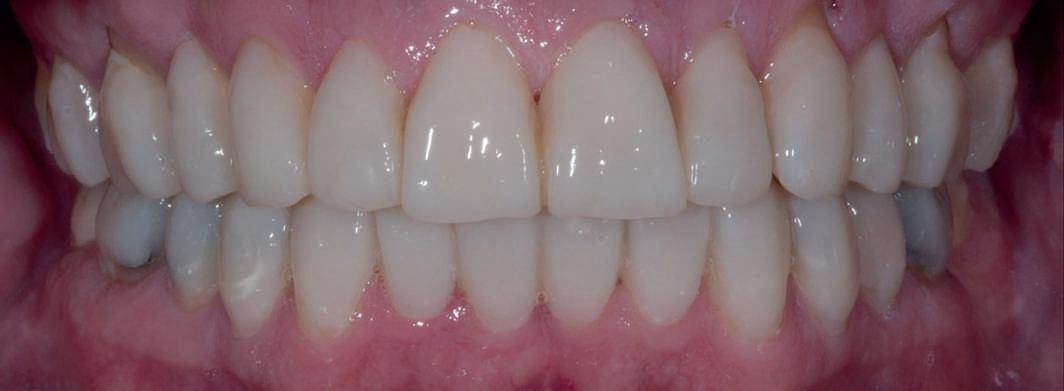

Acest pacient s-a prezentat cu o punte 1.3.-2.3. compromisă.

Pentru a păstra limitele restaurării fixe pe toată durata tratamentului, s-au inserat în primă etapă implanturi corespunzător 1.3. şi 2.3. După integrarea acestora, s-au aplicat bonturi individualizate, iar restaurarea provizorie s-a rebazat pentru suplimentarea suportului.

Implanturile şi bonturile ulterioare aferente s-au putut poziţiona în poziţiile 1.2. şi 2.1. Incisivul 1.1. a beneficiat de tratament endodontic electiv pentru a fi redus şi în cele din urmă, după inserarea bonturilor pe implanturile 1.2. şi 2.1., a fost scufundat (fig. 20, 21).

Atitudine: În fig. 21, este evident că, după submersiunea radiculară, nu se

obiectivează recesie în jurul bonturilor 1.2. şi 2.1. De notat osul excelent vestibular în dreptul tuturor implanturilor, fără recesie în jurul 1.3. şi 2.3. (fig. 22) care au fost inserate cu 8 luni înainte de 1.2. şi 2.1. Perioada scursă între scufundarea rădăcinii (fig. 20) şi inserarea punţii finale (fig. 22) a fost de 7 luni (fig. 23).

Figurile

20. Dintele 1.1. tratat endodontic.

21. Dintele 1.1. submersat în cele din urmă după inserarea bontului la nivel 1.2. şi 2.1.

22. Os excelent vestibular faţă de toate implanturile; nicio recesie la nivelul 1.3. şi 2.3. 23. Punte provizorie pe toate bonturile.